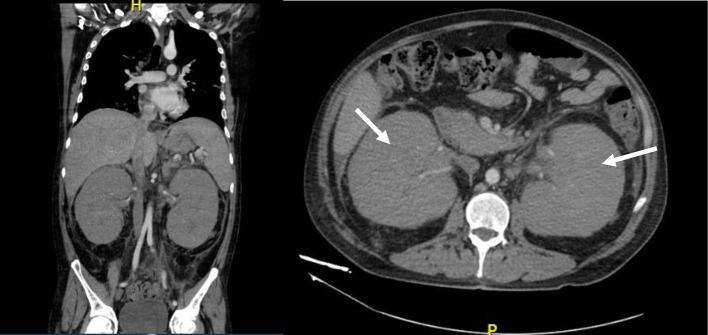

Acute lymphoblastic leukemia (ALL) is an aggressive hematological neoplasm typically more common in children than adults. More prolonged remissions and a potential cure can be achieved if allogeneic hematopoietic stem cell transplantation (allo-HSCT) is performed. Outcomes after allo-HSCT vary significantly among patients, and multiple factors contribute to these outcomes. Isolated extramedullary relapse (iEMR) after allo-HSCT is rare. We present the case of a 43-year-old man who was diagnosed with Philadelphia chromosome-negative (Ph-neg), B-cell ALL and underwent haploidentical allo-HSCT because of high-risk features at diagnosis. One year later, he was admitted to the hospital with facial and peripheral edema, proteinuria, elevated serum creatinine levels, and hypertension. Renal biopsy was performed immediately. Renal infiltration of TdT+ leukemic cells was detected by immunohistochemistry. Bone marrow aspiration, lumbar puncture, and computed tomography (CT) scans were performed to identify other sites of possible relapse. No other sites were identified, and an extramedullary isolated renal relapse was diagnosed. Intensive re-induction with chemotherapy was not possible because of the coronavirus disease 2019 (COVID-19) infection. Six weeks later, a medullary relapse was noted. Medullary infiltration of B-cell ALL after allo-HSCT has a historically poor prognosis; however, iEMR appears to have a better overall prognosis. The optimal treatment for renal iEMR is still a matter of debate.

急性淋巴细胞白血病(ALL)是一种侵袭性血液肿瘤,通常在儿童中比成人更常见。如果进行异基因造血干细胞移植(allo-HSCT),可以实现更长时间的缓解并有可能治愈。allo-HSCT后的结果在患者之间差异很大,多种因素导致了这些结果。allo-HSCT后孤立性髓外复发(iEMR)很少见。我们报告了一例43岁男性病例,他被诊断为费城染色体阴性(Ph-neg)B细胞ALL,因诊断时具有高危特征而接受了单倍体相合allo-HSCT。一年后,他因面部和外周水肿、蛋白尿、血清肌酐水平升高和高血压入院。立即进行了肾活检。通过免疫组织化学检测到TdT+白血病细胞的肾脏浸润。进行了骨髓穿刺、腰椎穿刺和计算机断层扫描(CT)以确定其他可能复发的部位。未发现其他部位,诊断为孤立性髓外肾脏复发。由于2019冠状病毒病(COVID-19)感染,无法进行强化化疗再诱导。六周后,发现髓内复发。allo-HSCT后B细胞ALL的髓内浸润历来预后较差;然而,iEMR似乎总体预后较好。肾脏iEMR的最佳治疗方法仍存在争议。